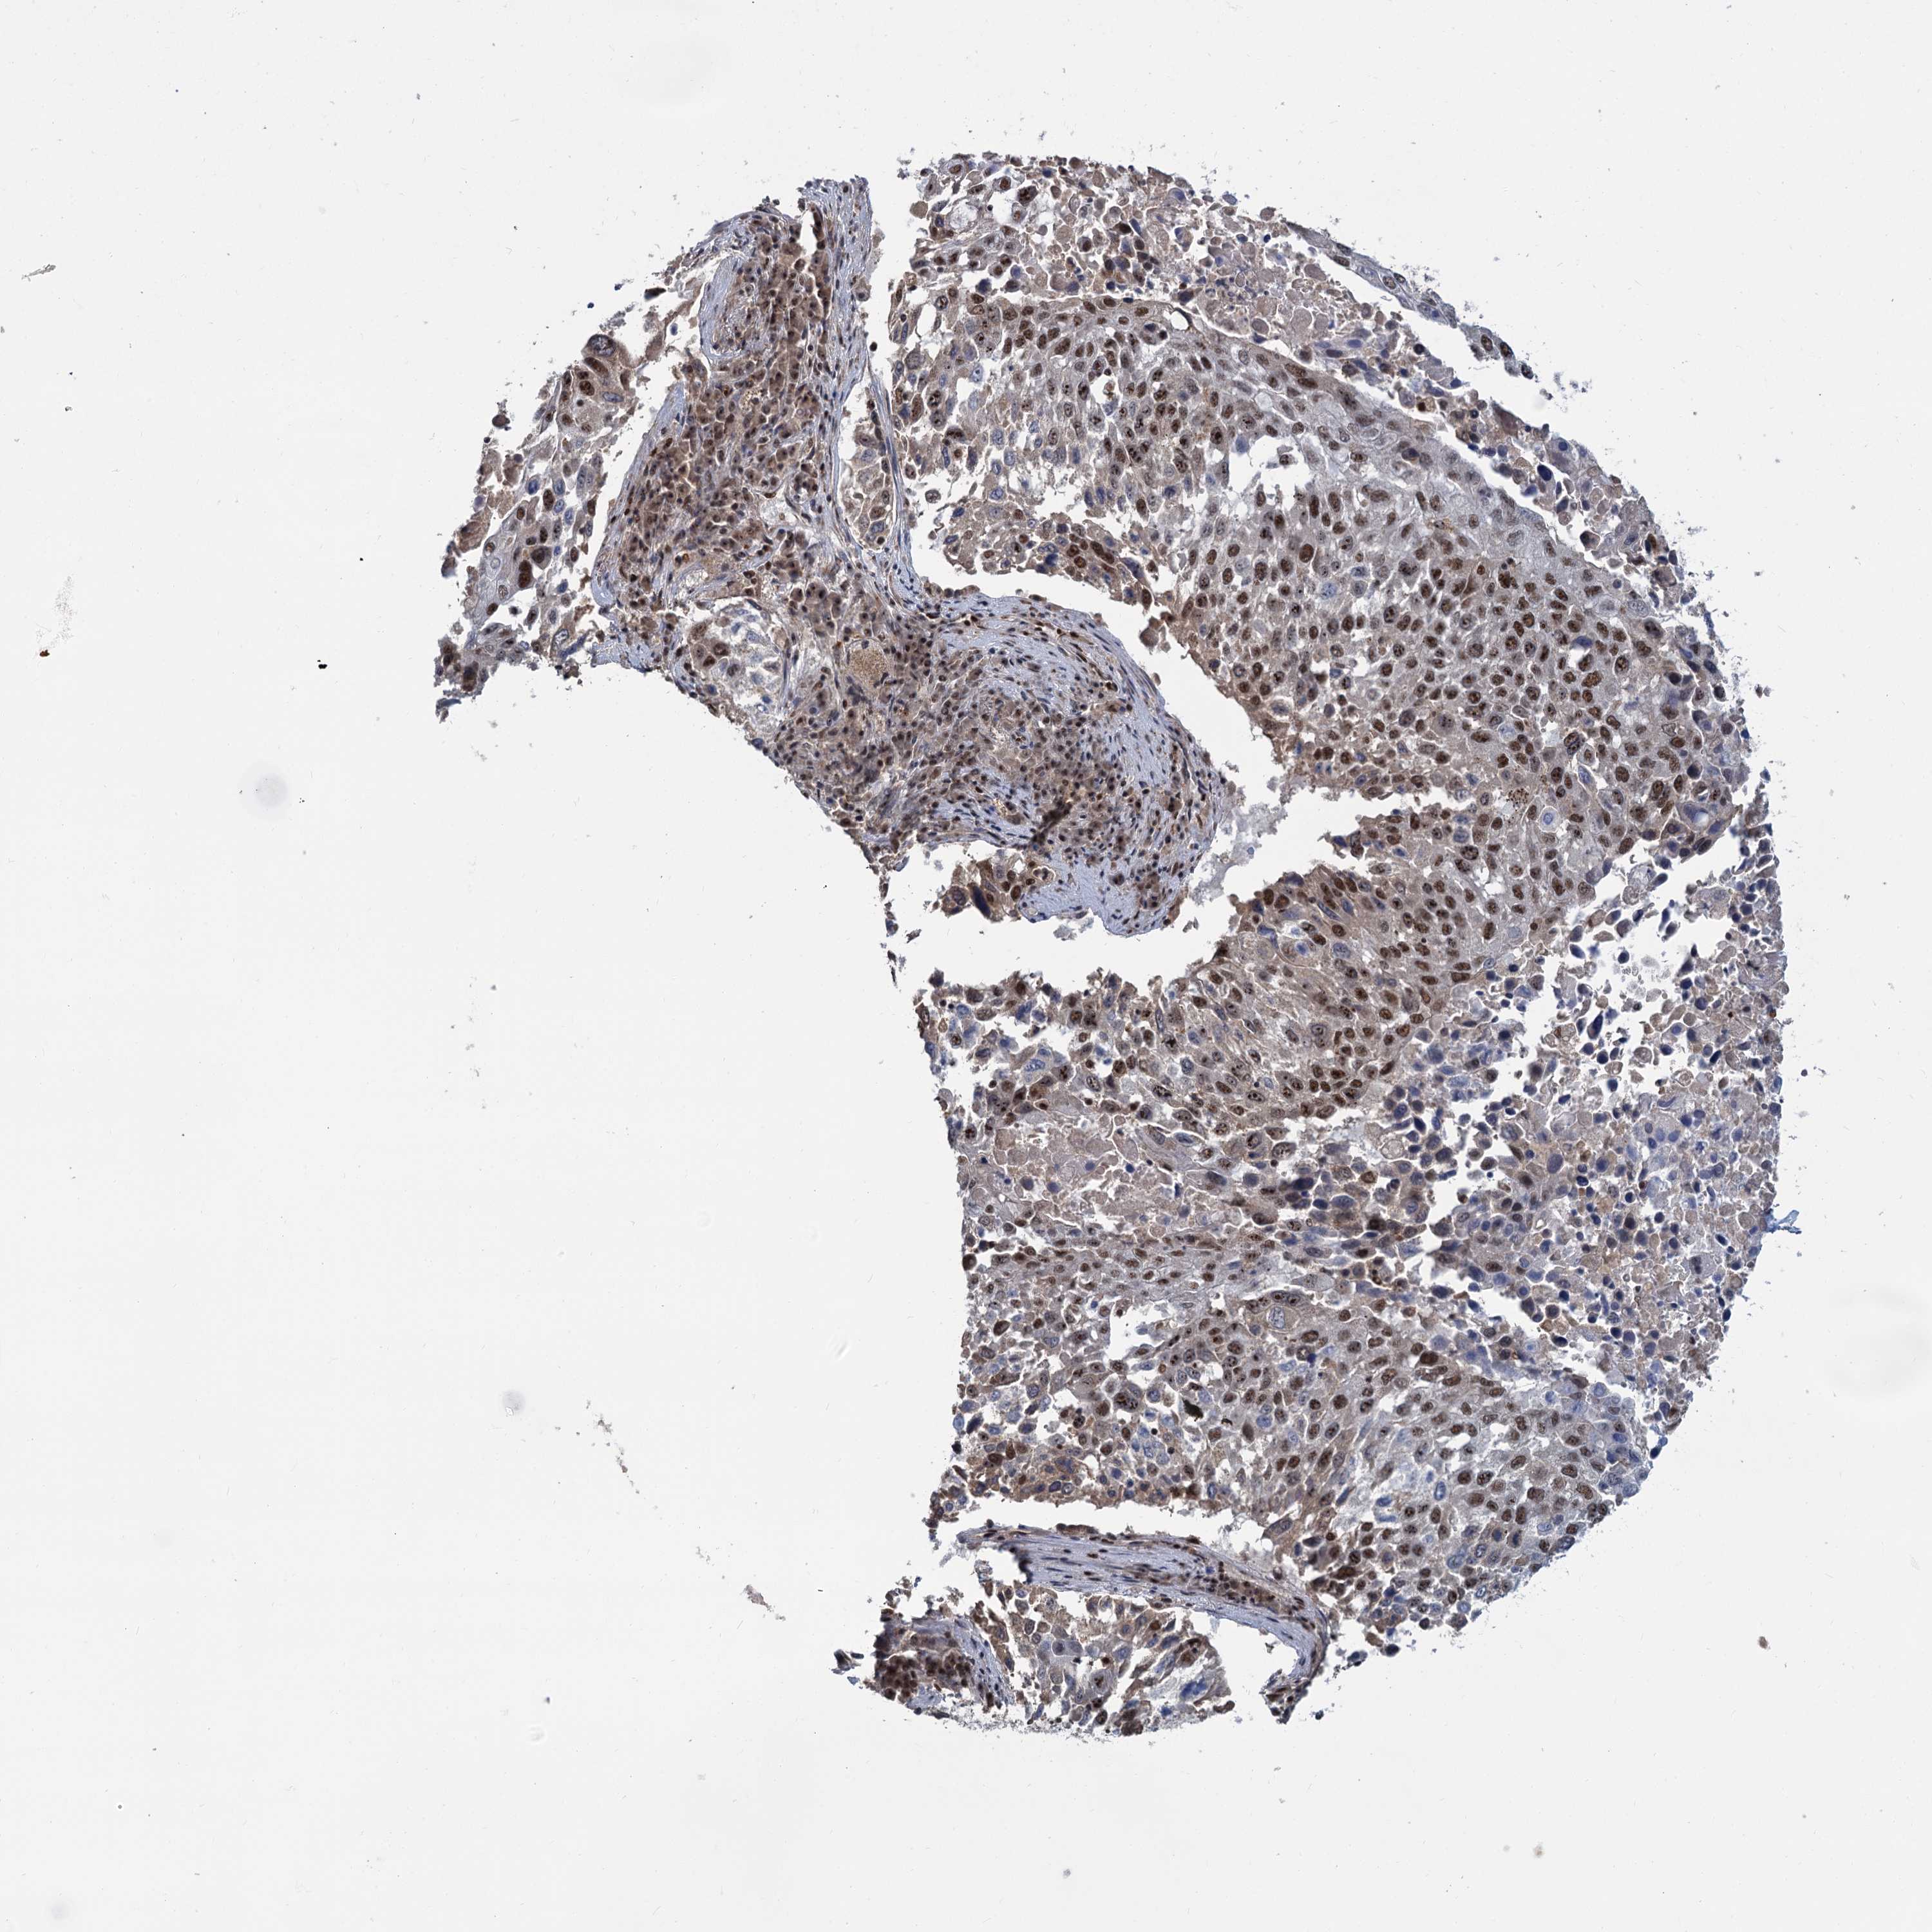

LUNG SQUAMOUS CELL CARCINOMA (TCGA) - Interactive survival scatter ploti

The Survival Scatter plot shows the clinical status (i.e. dead or alive) for all individuals in the patient cohort, based on the same data that underlies the corresponding Kaplan-Meier plots. Patients that are alive at last time for follow-up are shown in blue and patients who have died during the study are shown in red.

The x-axis shows the expression levels (FPKM) of the investigated gene in the tumor tissue at the time of diagnosis. The y-axis shows the follow-up time after diagnosis (years). Both axes are complimented with kernel density curves demonstrating the data density over the axes. The top density plot shows the expression levels (FPKM) distribution among dead (red) and alive patients (blue). The right density plot shows the data density of the survived years of dead patients with high and low expression levels respectively, stratified using the cutoff indicated by the vertical dashed line through the Survival Scatter plot. This cutoff is automatically defined based on the FPKM cutoff that minimizes the p-score. The cutoff can be changed by dragging the vertical line or by entering a cutoff value in the square labeled "Current cut-off".

Under the Survival Scatter plot the p-score landscape (black curve; left axis) is shown together with dead median separation (red curve; right axis). Dead median separation is the difference in median mRNA expression between patients who have died with high and low expression, respectively. It is calculated as follows: median FPKM expression of dead patients with high expression - median FPKM expression of dead patients with low expression. This is intended to aid the user in visually exploring custom cutoffs and the associated p-scores and dead median separation.

Individual patient data is displayed and can be filtered by clicking on one or more of the category buttons on the top of the page. Categories describing expression level and patient information include: high, low, alive, dead, female, male and tumor stages. The scale of the x-axis can be toggled between linear and log-scale by clicking on the "x log" button. Mouse-over function shows TCGA ID, patient information and mRNA expression (FPKM) for each patient.

& Survival analysisi

Kaplan-Meier plots summarize results from analysis of correlation between mRNA expression level and patient survival. Patients were divided based on level of expression into one of the two groups "low" (under cut off) or "high" (over cut off). X-axis shows time for survival (years) and y-axis shows the probability of survival, where 1.0 corresponds to 100 percent.

WBP4 is not prognostic in Lung Squamous Cell Carcinoma (TCGA)

: 10.28

P scorei

N/A

Average pTPM 8.4

Number of samples 489